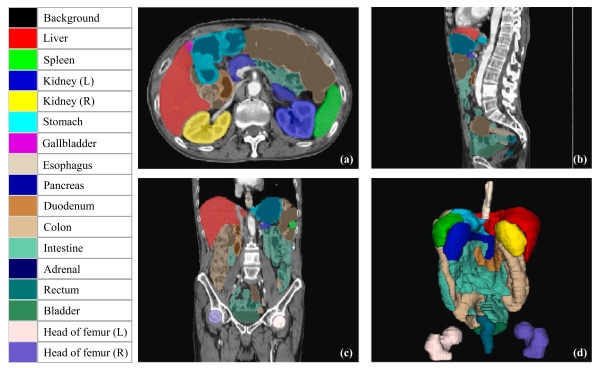

2,WORD Dataset [Downlaod]

This dataset contains 150 abdominal CT volumes. Each volume has 16 organs with fine pixel-level annotations and scribble-based sparse annotations. It can be used for study of automatic segmentation algorithms with fully supervised learning, semi-supervised learning and weakly supervised learning. References:

Xiangde Luo, Wenjun Liao, Jianghong Xiao*, Jieneng Chen, Tao Song, Xiaofan Zhang, Kang Li, Dimitris N. Metaxas, Guotai Wang*, Shaoting Zhang*.

WORD: A large scale dataset, benchmark and clinical applicable study for abdominal organ segmentation from CT image.Medical Image Analysis, 82 (2022): 102642

Meng Han, Xiangde Luo, Xiangjiang Xie, Wenjun Liao, Shichuan Zhang, Tao Snog, Guotai Wang*, Shaoting Zhang*.DMSPS: Dynamically Mixed Soft Pseudo-label Supervision for Scribble-Supervised Medical Image Segmentation.Medical Image Analysis, 97, October (2024): 103274.